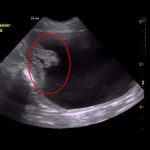

Can Bladder Tumors in Dogs Be Benign?

Yes, bladder tumors in dogs can be benign. Benign bladder tumors form when cells of the urinary tract grow and multiply abnormally, but they do not spread to other parts of the … [Read more...]